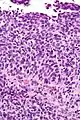

| Micrograph of transitional cell carcinoma of the ovary. H&E stain. |

TCC of the ovary is diagnosed by examination of the tissue by a pathologist. It has a characteristic appearance under the microscope and distinctive pattern of immunostaining.[2]

Low mag. Very high mag.

Very high mag.